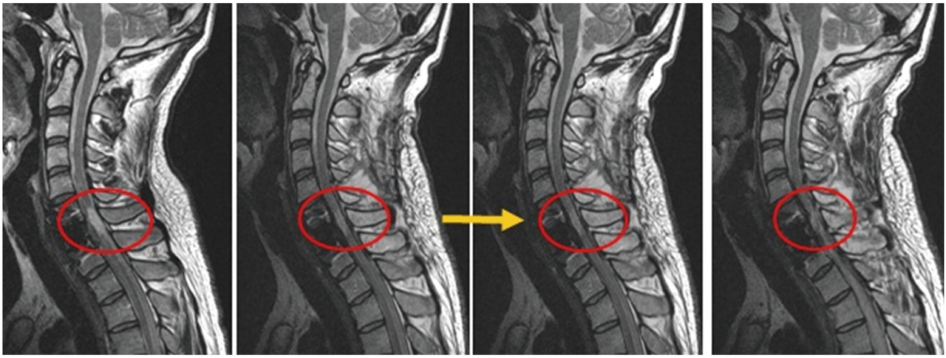

척추하반신 마비

Paraplegia

MRI상 병변 부위가 점차 짙어지는 것이 보여집니다.

이는 병변 부위가 호전되는 것을 의미합니다.